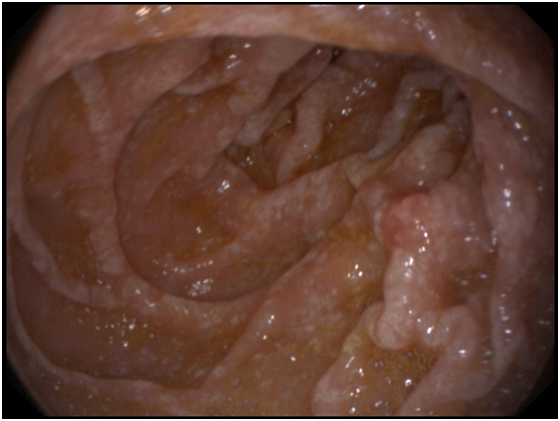

A 53- years old male presenting with chronic diarrhea of 8months duration, his diarrhea was of large volume, frothy in nature with foul odour. It was not related to a specific type of food, persisted during fasting with no diurnal variations. His condition was also associated with significant weight loss. The condition was associated with low grade fever and arthralgia of his both knee and hip joints. After 2months from the onset of his diarrhea he started to develop dizziness and easy fatigability. Physical examination of the patient was unremarkable apart from the pallor. Work up for diagnosing the cause of his diarrhea was done in the form of repeated stool analysis and culture, complete blood count, liver profile, renal profile, electrolytes, ESR, B2 microglobulins, virology (HIV, HBsAg, antiHCVab) and thyroid profile. All the previously mentioned investigations were normal apart from microcytic hypochromic anemia due to iron deficiency with haemoglobin=7.3mg/dl, serum Fe was 10mg/dl and transferrin saturation was 5%, also he had mild hypoproteinemia with serum total protein of 6.2g/dl and mild hypoalbuminemia with serum albumin of 3g/dl. His ESR was 123 and C-reactive protein (CRP) was 49mg/dl as shown in Table 1. Abdominal ultrasound was completely normal. Attempts of giving empirical medications in the form of metronidazole and quinolones failed to control the condition of the patient. Endoscopic intervention was decided in the form of upper endoscopy and colonoscopy. Total colonoscopy and terminal ileoscopy were done with no abnormality detected. For the upper endoscopy; the duodenal mucosa down to the proximal jejunum was markedly congested with extensive whitish mucosal patches as shown in Figure 1-3. Multiple biopsies were taken; histopathological examination showed focal villous distortion and focal villous erosions. The lamina propria showed mild mono-nuclear cell infiltrate with extensive infiltrate of foamy macrophages with dilated lymphatic spaces as shown in Figure 4. PAS (periodic acid shiff) stain was applied during microscopic examination where the organism was detected as shown in Figure 5. And hence the patient was diagnosed as a case of Whipple’s disease (WD). Then treatment was started accordingly in the form of ceftriaxone for 15days followed by trimethoprim-sulfamethoxazole (TMP/SMX) twice a day for 1 to 2years with marked improvement of the patient's condition. The improvement was evident by his laboratory parameters (Table 1) and endoscopic picture (Figure 6).

Figure 1 Shaggy mucosa of the duodenum.

Diagnosis is made from duodenal biopsy, taken by upper endoscopy, which reveals pale yellow shaggy mucosa with erythematous eroded patches in patients with classic intestinal Whipple's disease25 and this is seen in our patient. Histopathological examination of the duodenal biopsies shows infiltration of the lamina propria with PAS-positive macrophages with intracellular clumps of T. whipplei.3 Immunohistochemical staining for antibodies against T. whipplei has been used to detect the organism in a variety of tissues, and a PCR-based assay is also available.26 Electron microscopy can be diagnostic showing coccobacillary bodies that represent the T. whippeli organism. Histologic examination with routine H&E and PAS stains is usually sufficient to reach a diagnosis, however, it is recommended that PAS-positive histologic findings to be confirmed with other methods when establishing the diagnosis of WD.25,26